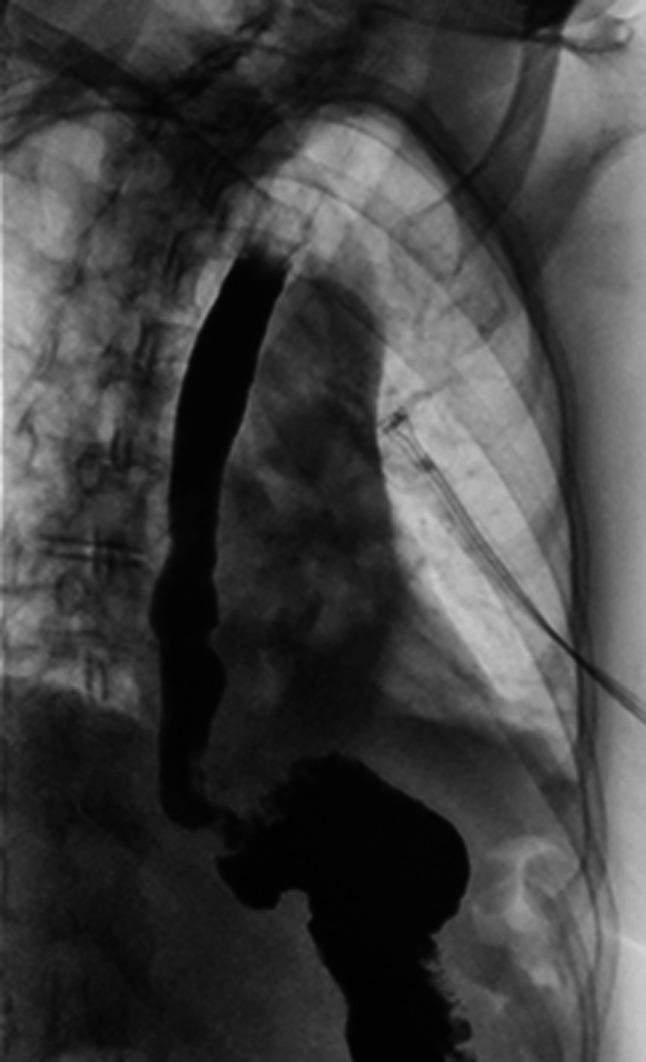

Esophageal diverticulum (ED) is a rare condition with a clinical presentation that can be variable. Esophageal diverticulum has been associated with motility disorders; however, the association with mid-ED is less clear. Hypercontractile esophagus, also known as jackhammer esophagus, is a rare motility disorder of peristalsis diagnosed by esophageal high-resolution manometry after exclusion of mechanical obstruction. We describe the second reported case of mid-ED secondary to hypercontractile esophagus successfully treated through robotic diverticulectomy with long myotomy. KEYWORDS: esophagus; esophageal manometry; motility; diverticular disease.

食管憩室(ED)是一种罕见疾病,临床表现多变。食管憩室与动力障碍有关;然而,与中段食管憩室的关联尚不清楚。高收缩性食管,也称为风钻食管,是一种罕见的蠕动动力障碍,在排除机械性梗阻后通过食管高分辨率测压诊断。我们描述了第二例因高收缩性食管继发中段食管憩室的病例,该病例通过机器人憩室切除术加延长肌切开术成功治疗。关键词:食管;食管测压;动力;憩室病